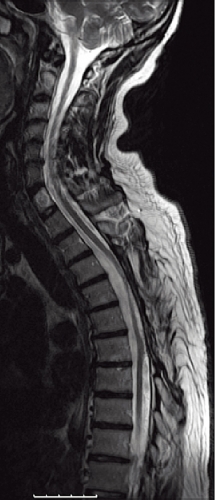

Uppföljning med spinal angiografi ett år senare visade ingen kvarvarande arteriovenös fistel. På MRT 18 månader efter behandlingen sågs inget ryggmärgsödem, och de perimedullära venerna hade tydligt minskat i diameter (Figur 5). Patienten återfick i mellantiden en stor del av sin motoriska funktion och klarade bl a att gå utan rollator. Besvären med urin- respektive avföringsinkontinens förbättrades kraftigt liksom känseln i bägge benen.

Diagnostik. Den kliniska bilden och spinal MRT är helt avgörande för diagnosen. Okunnighet hos kliniker eller radiolog kan få som konsekvens att diagnosen ställs för sent eller inte alls, medan patienten utvecklar en obotlig parapares. De typiska fynden vid MRT är ödem och lätt svullnad av ryggmärgen torakolumbalt samt vidgade blodkärl (vener) dorsalt perimedullärt. Ödemet uppvisar hög signal centralt i ryggmärgen på T2-viktade bilder. De vida perimedullära venerna syns i cerebrospinalvätskan som slingriga strukturer med låg signal på T2-viktade bilder och hög signal på T1-viktade bilder efter intravenös kontrastmedelstillförsel.